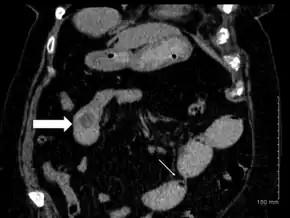

Diagnosis of gallstone ileus requires radiographic studies. Classic radiographic findings are known as Rigler's triad:[6]

- pneumobilia (air within the biliary tree)

- evidence of small bowel obstruction

- radiopaque gallstone on abdominal radiograph